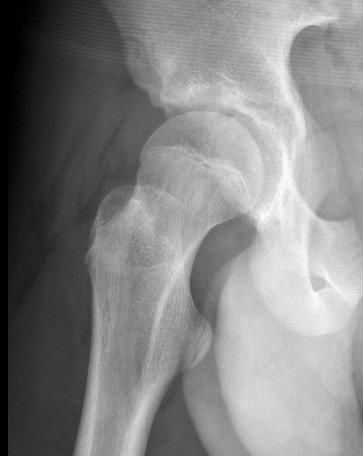

Pubic symphysis diastasis

Assess

- urological injury

- posterior ring injury

Treatment

- heals with periosteal sleeve

- if wide should close with external fixator

- if remains widened child walks with external rotation deformity